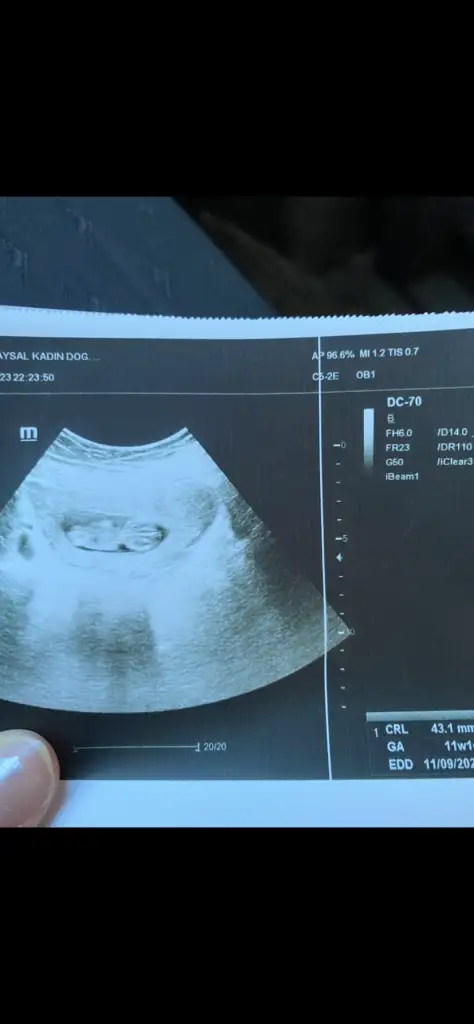

Cinsiyet tahmininden anlayan arkadaşlar yorumlarınızı bekliyorum

Benim bebeğimin cinsiyeti nedir sizce ☺️

Buda 11 haftalık olan çok merak ediyorum bakalım ne olucak 🥰